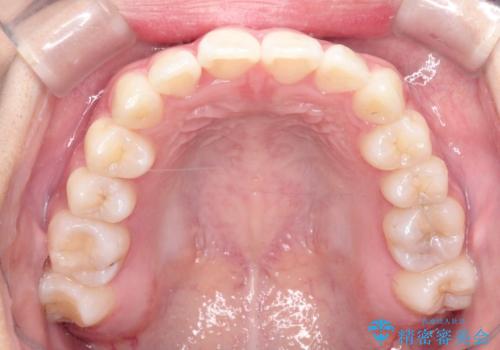

前歯のがたがたを綺麗にしたい

- 前歯がねじれていること、出ていることを主訴に来院されました。

前歯の突出感も改善され、満足していただきました。